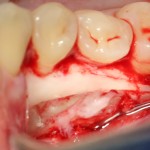

А вот их лунки:

Теоретически, лунки можно чем-нибудь заполнить. Только чем? И для чего?

Костная ткань сама регенерирует, если ей не мешать. Поэтому не стоит толкать в лунки какой-нибудь остеопластический материал, типа Cerabone или Bioss. Нет смысла.

В данном случае я использовал обычную коллагеновую губку — и то, только для того, чтобы «костная дверца», которую я выпилил в самом начале операции, не провалилась внутрь:

Теперь запиливаем «костную дверцу» на ее законное место: